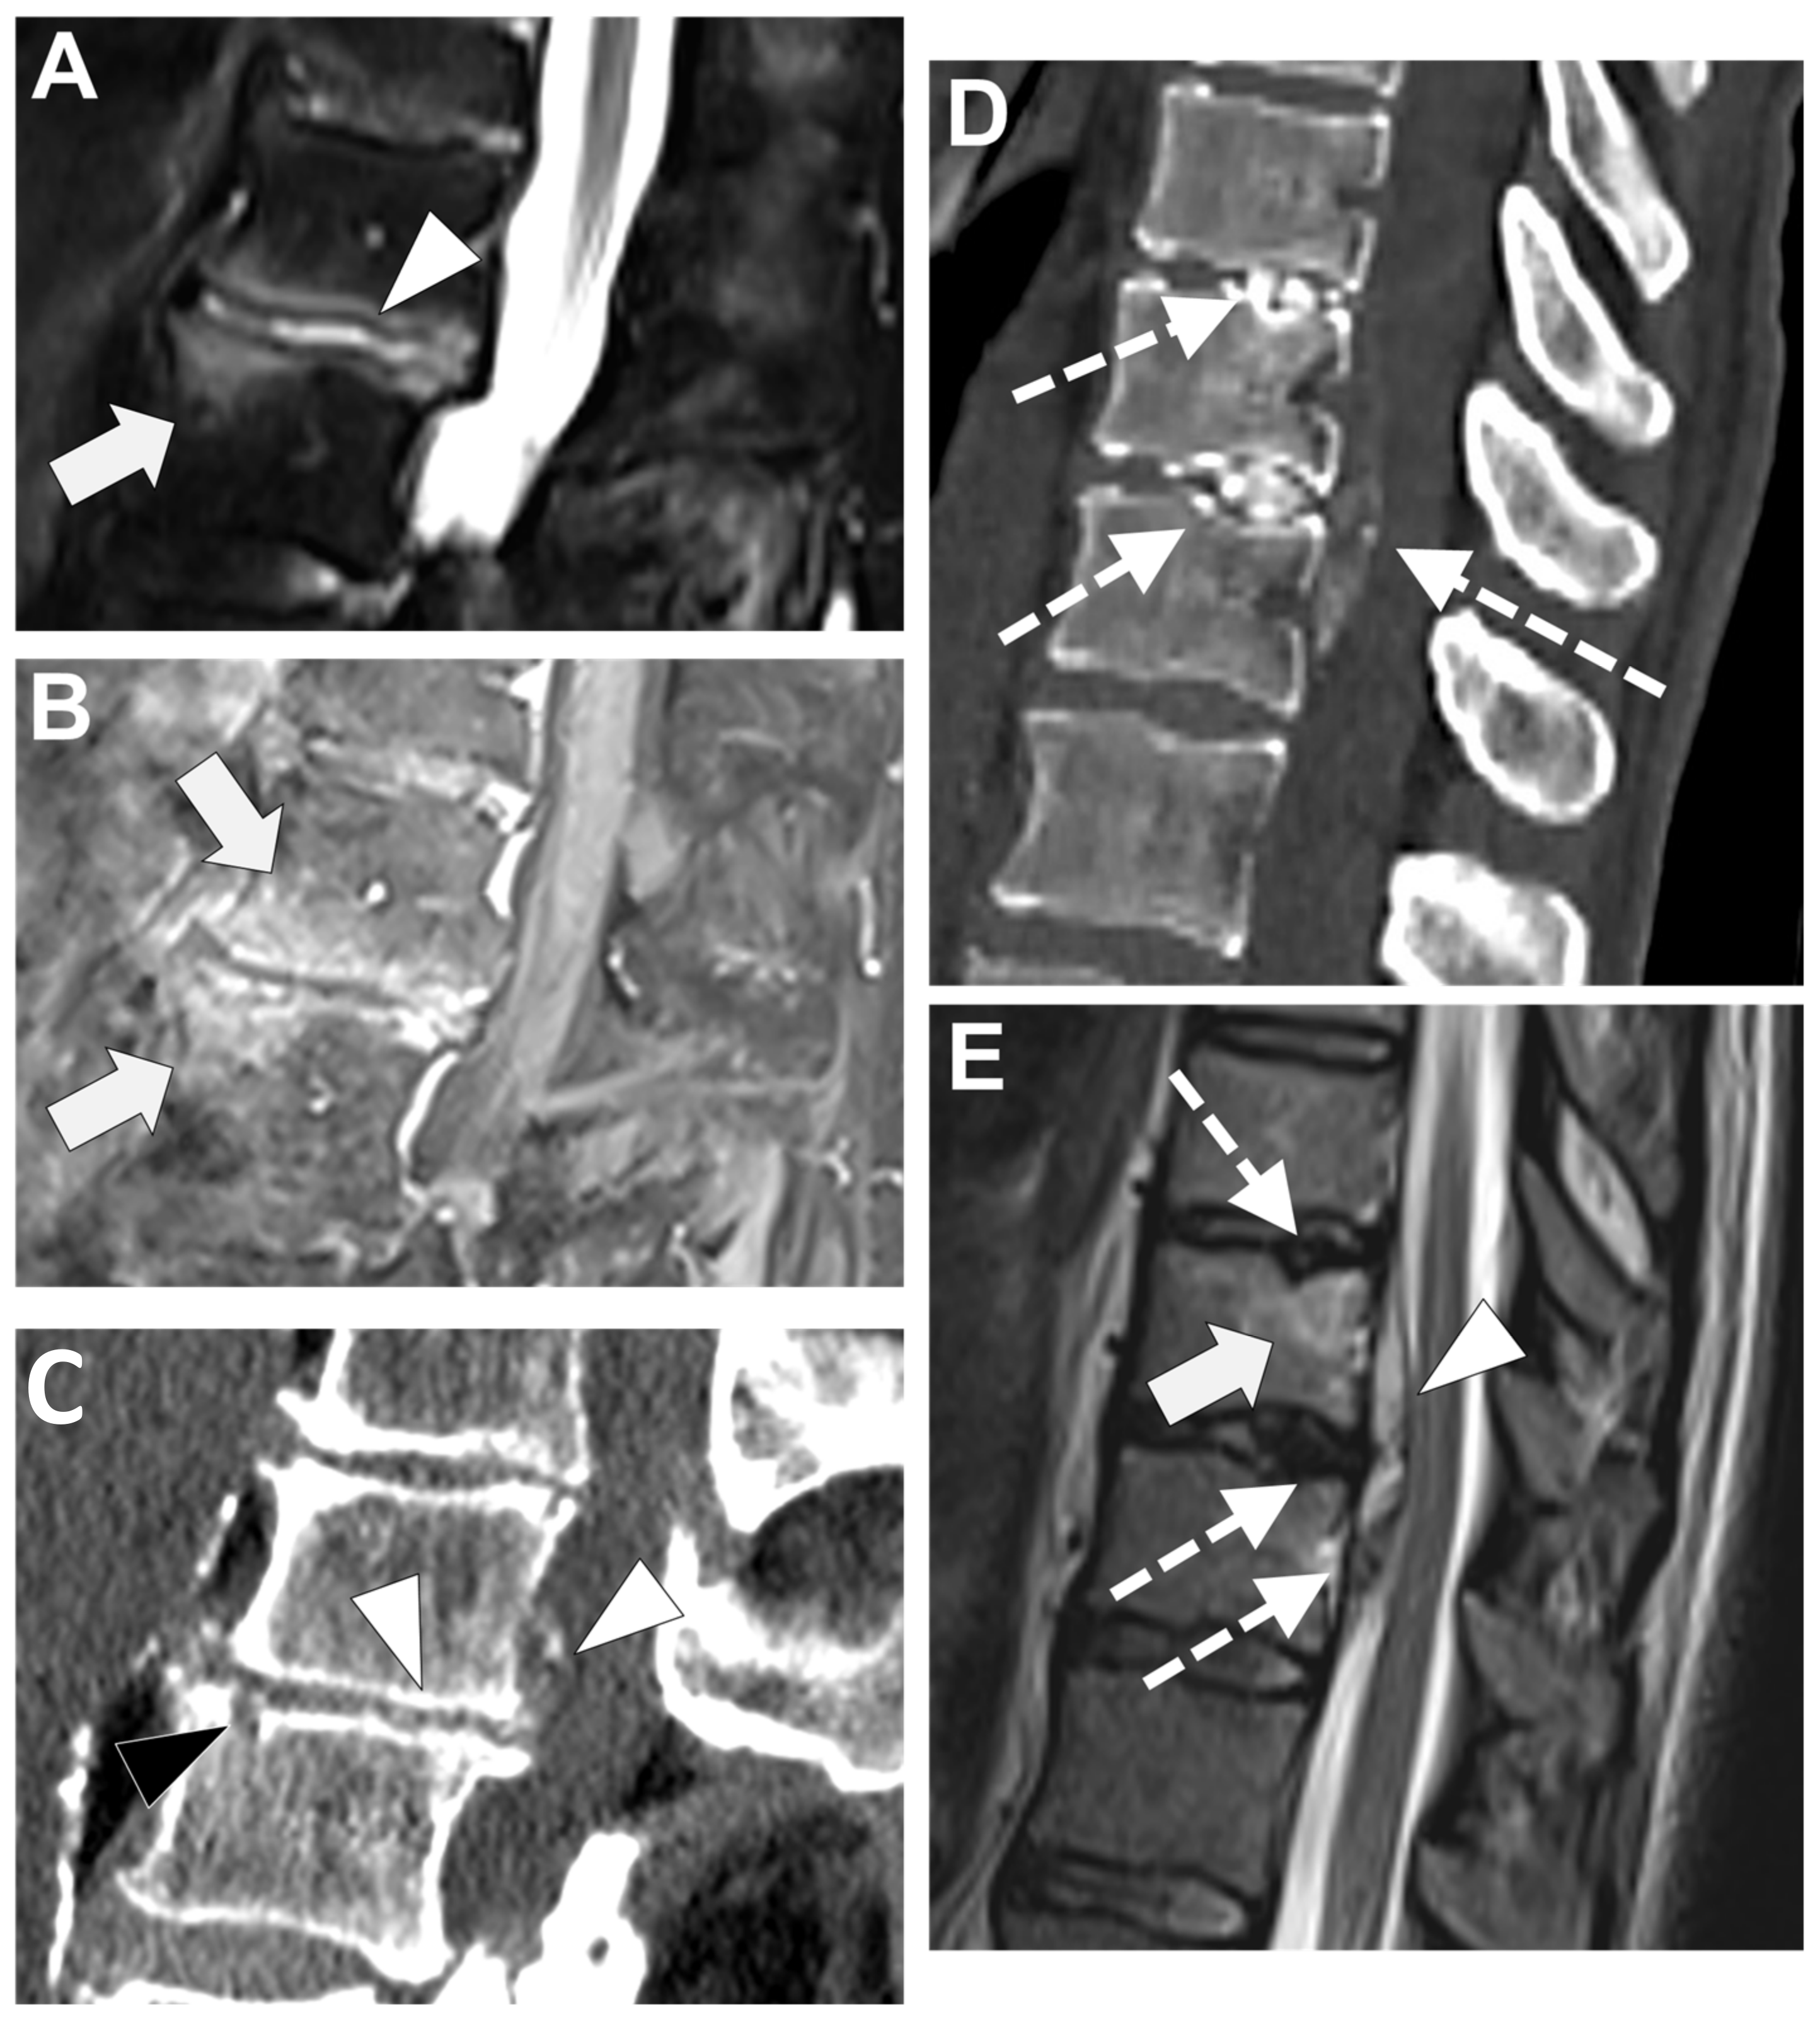

In Figure 6 an exemplificative case of TbS is presented.

In Figure 7 an exemplificative case of PyS is presented.

Figure 6. Tubercular spondylodiscitis. A 24-year-old man of Sudanese origin presented with thoracic and lumbar pain evolving for several months. An MRI was performed with (A) T2-weighted imaging (WI) and (B) contrast-enhanced (CE) T1-WI, as well as a CT-scan in bone kernel (C) and abdominal kernel after contrast medium injection (D,E). It demonstrates preserved disk but extensive sub ligamentous collections spreading along the anterior side of the thoracic and lumbar vertebral bodies (white arrowhead), but also along the posterior vertebral collateral ligament (white arrows) with large anterior and posterior erosions (black arrows). Please note the extensive collections spreading in the presacral space and along bilateral iliopsoas muscles without surrounding inflammation (white dashed arrows).

Figure 7. A 73-year-old male presented with a rapidly evolving lumbar pain and fever, with an inflammatory syndrome on blood samples. A first MRI was performed as infectious spondylodiscitis was suspected, which included (A) STIR T2-weighted imaging (WI) and (B) fat sat T1-WI after gadolinium chelates injection. It shows a high signal intensity (SI) of the L3-L4 disc while other disks are in lower signal (black arrowhead), as well as linear subchondral contrast enhancement (CE) of the L3-L4 endplates both linear and more pronounced at the upper anterior corner of the L4 vertebral body (white arrowheads). Moreover, the left T11-T12 facet joints displayed marked edema of the subchondral bone and surrounding tissues (white arrows). A control MRI with SITR T2-WI (C) and fat-suppressed CE-T1-WI (D) was performed one month later, demonstrating a marked narrowing of the L3-L4 disk (black arrowhead), erosions of the vertebral body (dashed white arrows), extensive edema in the L3 and L4 vertebral body (white arrowhead), a persisting arthritis involving the left T1-T12 facet joint. Bacillus cereus was found on the Bacterial analysis of the L3-L4 disk biopsy.